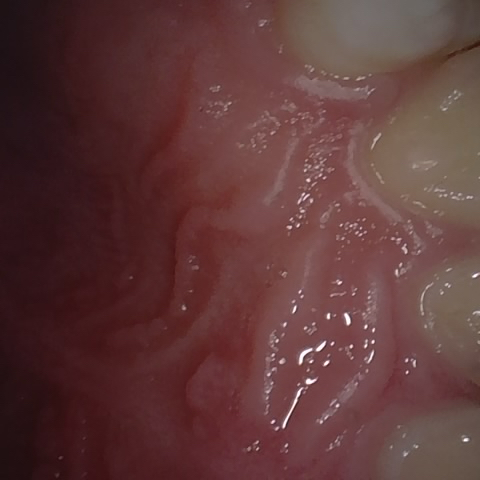

Annotated as "Good"